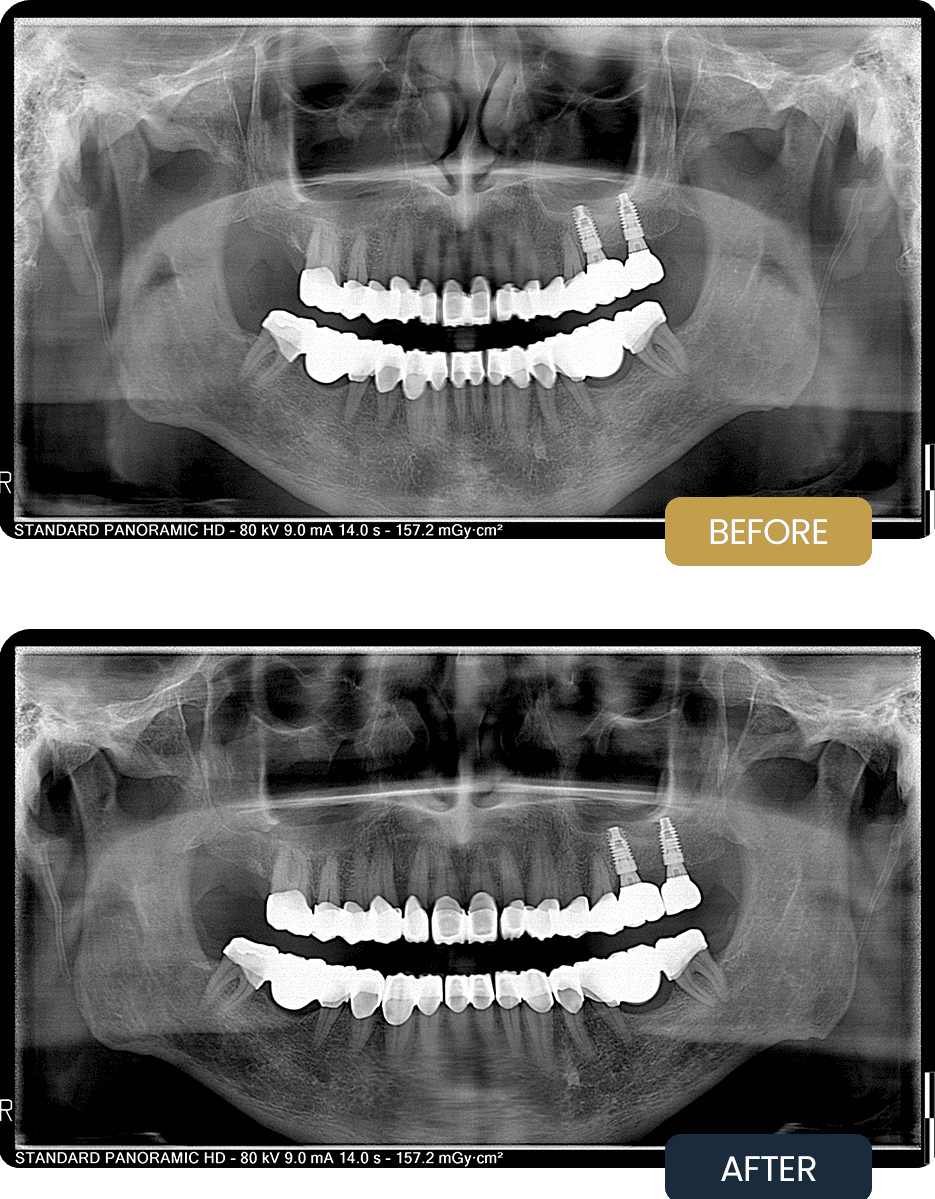

At presentation for aftercare, Shaun reported issues related to cracked crowns affecting comfort and function. Radiographic evaluation confirmed stable implant integration in the upper jaw, with prosthetic complications limited to the crown restorations.

The pre treatment panoramic image illustrates the condition of the restorations prior to aftercare intervention and the need for prosthetic correction rather than implant replacement.

AFTER

Post treatment panoramic imaging confirmed stable implant positioning and well seated new crown restorations with improved occlusal balance. The replaced crowns demonstrated proper alignment and structural integrity.